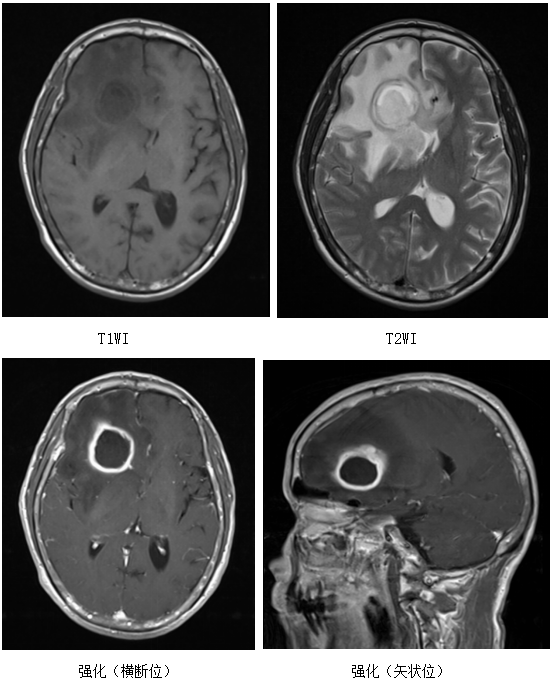

病例九患者张先生,60岁,查头颅ct提示:左侧颞叶脑胶质瘤.